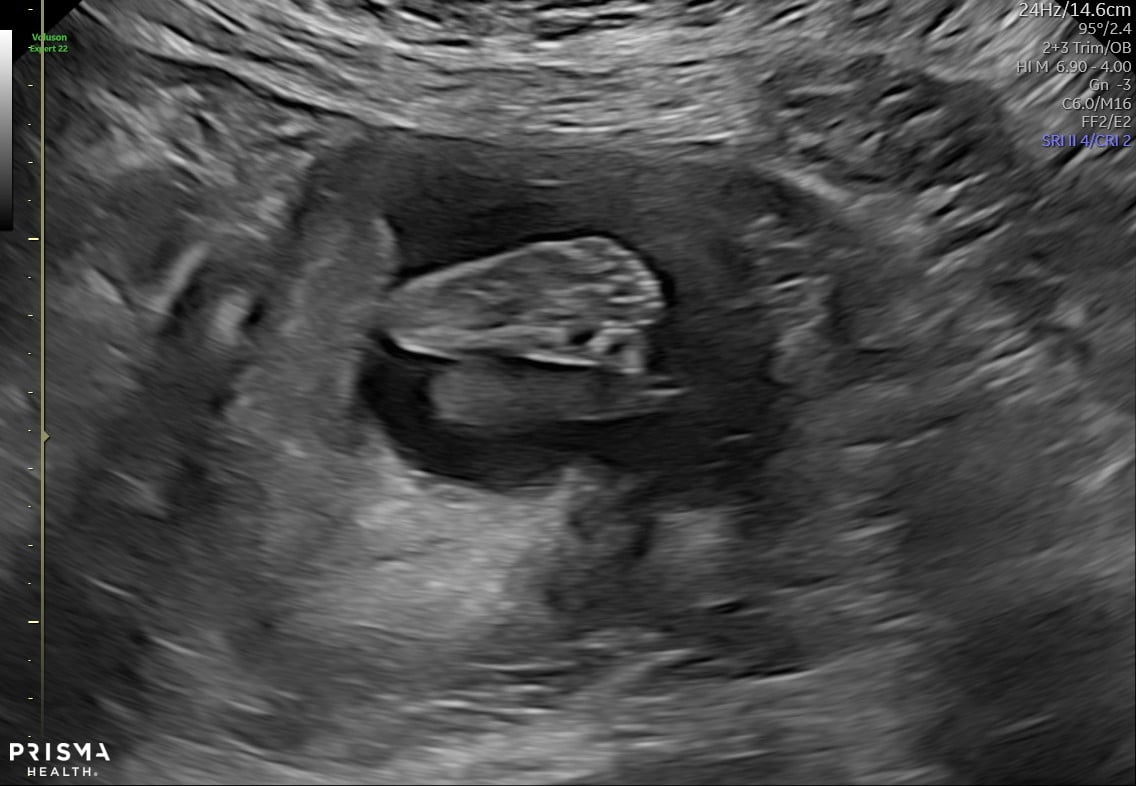

Here’s our little Squirt! 12w on the dot yesterday. I was diagnosed with a subchorionic hemorrhage which I guess will resolve itself. Thrilled to see that we’re actually looking like an infant!!